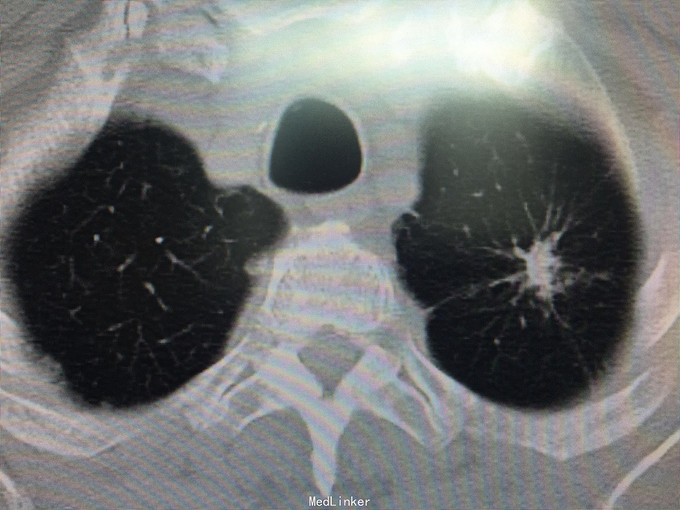

男性,70岁, 主诉:发现左肺上叶占位12个月 现病史:2014.10月患者出现胸背部疼痛不适,对症理疗未见好转。2014.11月出现咳嗽,咳痰带血丝,行胸部CT检查示:左肺上叶占位病变,恶性可能性大。2014.11.13患者行PET/CT检查提示:左肺上叶软组织密度肿块影伴周围片状密度增高影,代谢增高,考虑恶性病变伴周围炎性改变。纵隔内及左肺门多发淋巴结影,代谢增高,考虑为恶性病变转移。左肾上腺结节,代谢增高,考虑为恶性病变转移。第2胸椎棘突骨质破坏,代谢增高,考虑为恶性病变转移。肿瘤标志物:CA125 625 U/ml。因肿块位置较高,未行纤维支气管镜取病理,患者因年龄大,拒绝行肺肿物穿刺活检,故病理不明确。但根据肿瘤影像学形态及理化检测,怀疑为腺癌,建议患者行TKI靶向治疗,同时给予双磷酸盐治疗骨转移。患者口服TKI一个月后复查胸部CT肿块明显缩小,胸背部疼痛消失。患者现口服TKI约11个月,无明显咳嗽咳痰,无背部疼痛。近1周,患者诉偶尔咯鲜红色粘痰,伴有咽部及胸前区闷痛疼痛无明显咳嗽症状,为求复查而来诊。复查胸部CT较之前对比未见明显变化。复查肿瘤标志物:CEA、CA-125、NSE均未见异常。

查体:BP 165/75mmHg,双肺呼吸引清,未闻及干湿罗音,心音钝,心律齐,心率72次/分,各听诊区未闻及杂音。腹平,未见胃肠型及蠕动波,腹软,全腹无压痛,无反跳痛及肌紧张,肝脾肋下未触及,墨菲氏征(-),移动性肝肾区无叩痛,移动性浊音(-),肠鸣音4次/分。 辅助检查:肝胆脾彩超:未见明显异常。 胸部CT:较2015.8月对比未见异常,左肺上叶陈旧性改变。 肿瘤系列:CEA、CA-125、NSE均未见异常。